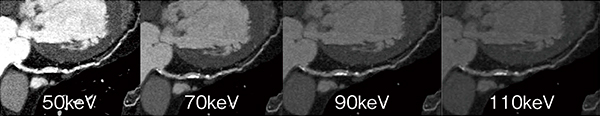

Cardiac Imagingにおいて,低エネルギーkeV画像はコントラスト差が大きくプラーク診断に有用であり,高エネルギーkeV画像はビームハードニングの影響を抑えたステント内腔の評価に有用である(図2)。同時に,両エネルギーの時間位相差のないraw dataが得られることで,“水”と“ヨード”に着目した計算から,物質の密度値や密度画像を構築することが可能である。心臓領域においては高度石灰化の近傍評価などに有用で,冠動脈石灰化の主成分とされるハイドロキシアパタイト(HAP)などの密度値をNullにしたヨード密度画像にて,石灰化からの影響を受けず内腔の診断が可能となる(図3)。この密度画像は,近年注目されるプラークの性状診断や心筋Perfusionにおいても有用性が期待されている。シングルエネルギーやCT値ベースのデュアルエネルギーではビームハードニングの影響を強く受ける下行大動脈と左室の間の領域においても,GSI Cardiacのヨード密度画像を用いることでビームハードニングによるCT値シフトの影響を受けず,精度の高い虚血診断能が期待される(図4)。

図2 モノクロマティック画像